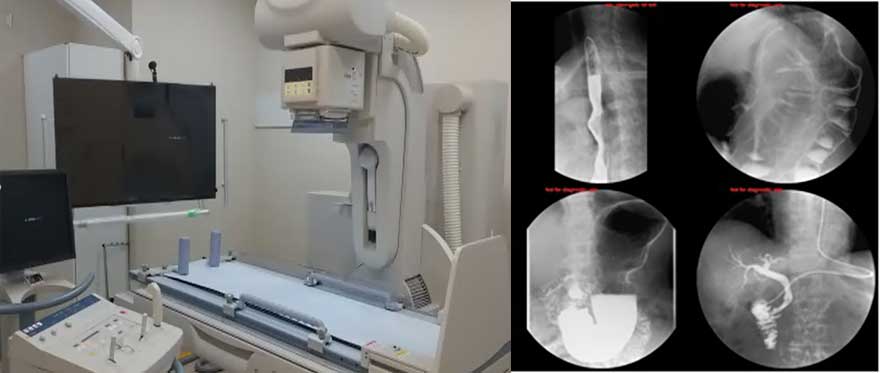

X線TV装置(X線透視)

- canon社製 ZEXIRA™

胃や腸のバリウム検査をはじめ、骨折の整復術、透視下内視鏡検査(ERCPなど…)など、

リアルタイムに様々な画像を見ながらの検査に使用します。